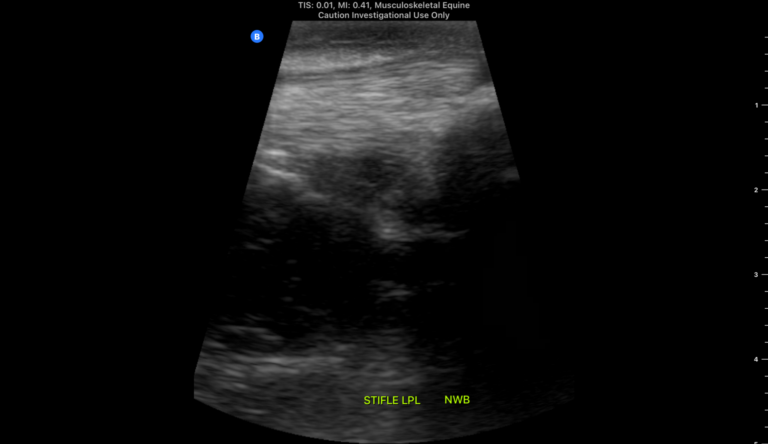

Lateral Patellar Ligament Non Weightbearing

Butterfly Equine Ultrasound Tips: Non-Weightbearing or Flexed Ultrasonography